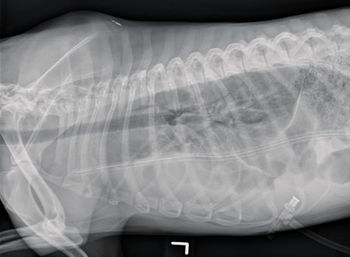

Ingested fur proved too large to remove by scope.

A Y-U pyloroplasty is a great technique for treating this condition-when done with the utmost care and precision.